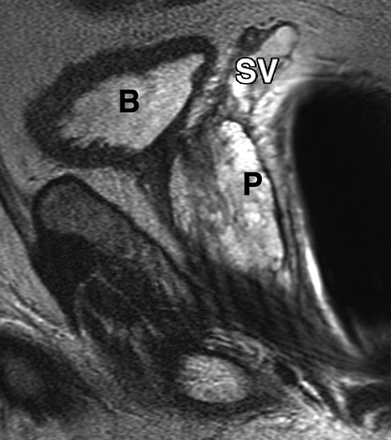

Most prostate cancers arise in the peripheral zone (PZ) [5], a region that may be compressed by the expanding transition zone (TZ) when there is significant BPH.

To improve PZ sampling it has been proposed that needle placement for systematic biopsies be directed more laterally [6], so that the biopsy tract traverses more of the PZ and encompasses the lateral PZ.

Although most prostate cancers originate in the PZ, up to 24% may arise in the transition zone (TZ) [5] and would therefore be missed by any biopsy protocol that sampled only the PZ.

Sextant biopsies were taken routinely ≈ 1 cm apart in the parasaggital plane bilaterally, at the base, mid-gland and apical regions of the prostate, as described by Hodge et al. [1]. In addition, six further biopsies were obtained, two from the TZ and four from the lateral PZ, as depicted in Fig. 1. The TZ biopsies were taken at the level of the mid-gland where the TZ was most prominent. The lateral PZ biopsies were taken by positioning the probe just medial to the lateral edge of the prostate at the base and mid-gland regions bilaterally, as described by Chang et al. [8]. This method generally allowed any area of DRE abnormality or suspicious hypoechoic lesion noted on TRUS to be incorporated into the biopsy protocol. All patients underwent the same biopsy strategy with no variance for gland size. Biopsies were obtained using an 18 G core-biopsy needle mounted on a spring-loaded automatic biopsy gun. All patients were placed in the left lateral decubitus ('knee-chest') position and all were examined with no prior bowel preparation. The procedure was generally well tolerated and no patient required intravenous sedation or narcotic analgesia. All TRUS was undertaken by the same operators (D.R.G. and N.S.), either personally, or when supervising a higher urological trainee.